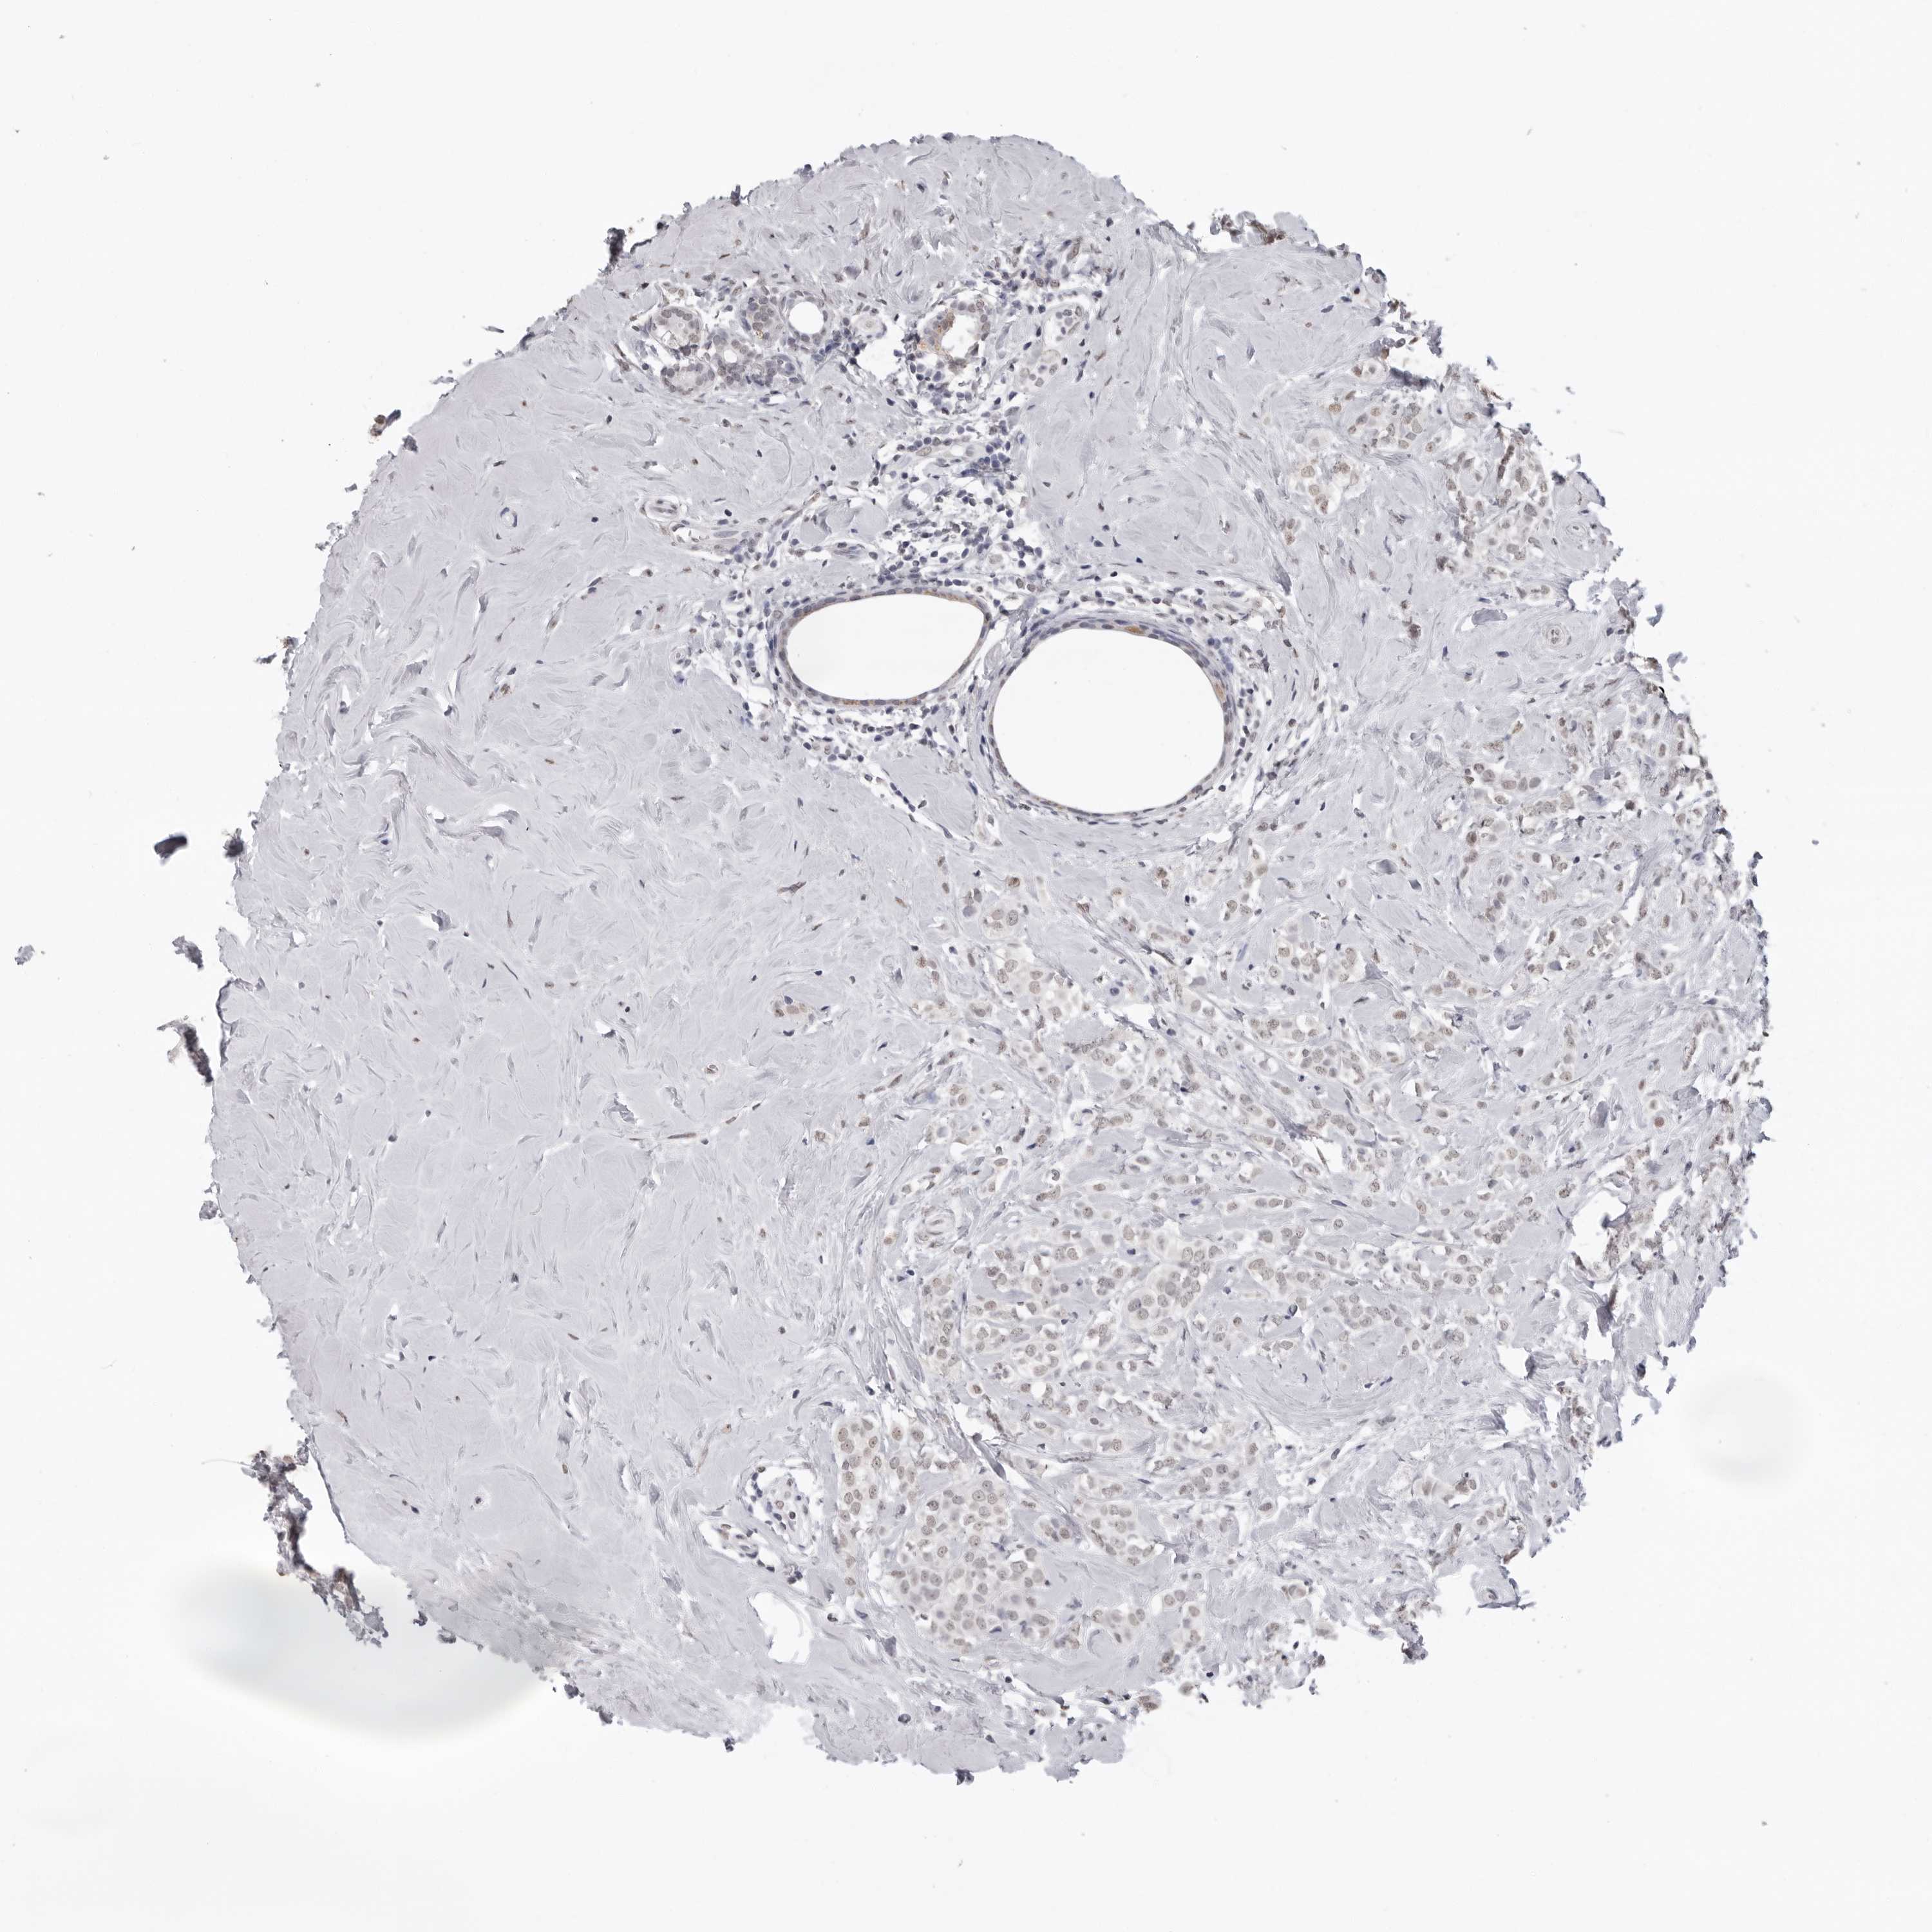

CANCER BREAST CANCER Show tissue menu

BRCA TCGA BRCA VALIDATION PROTEIN EXPRESSION